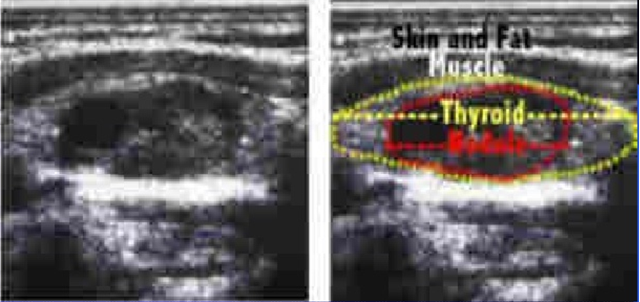

- US: Solid/ cyst / art of MNG/ LAP

- US thyroid